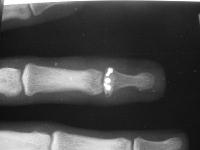

The injury:dorsal DIP fracture dislocation of the ring finger of a 16 year old male sports hopeful.

Unstable even in a well molded splint.